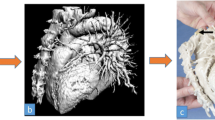

The physical model of the liver is created using 3D printing technologies to produce the vasculo-biliary branching and 3D moulding to reproduce the parenchyma, using the same approach reported in our previous work [21]. We exploit an in-house developed manufacturing protocol based on the 3D assembly of vasculo-biliary branch models inside a dedicated mould that reproduces the parenchymal morphology, as shown in Fig. 55.11. After assembling the vascular system while keeping the correct anatomical configuration and relative spatial features (i.e. distances between vascular branches, mutual position between vascular and biliary trees), a tissue-equivalent silicone-based blend is poured into a custom-designed mould, giving shape to the parenchymal structure and embedding the intrahepatic arterial–venous branch and the biliary duct.

We manufactured the portal and hepatic veins, and the hepatic arteries as hollow vessels to reproduce the haptic response of biological vessel walls, while for the biliary tree, characterised by small-diameter branches, we preferred a solid structure allowing the model to be self-standing and more robust, as shown in Fig. 55.12. They were directly printed, choosing a commercial 80 ShoreA and 8.9 MPa ultimate tensile strength low-hardness photopolymer [61] with 0.1 mm layer resolution to create accurate and robust smooth surface finished parts.

We also printed a second replica of the vasculature branching, in this case without the surrounding parenchyma, using the same UV-curable resin and equipped with detachable connecting pins to allow surgeons to handle the phantom, even with the possibility of separating and subsequently reassembling the components for improved visualisation purposes.

We chose ABS thermoplastic to produce the 3D mould required to assemble the structures and cast the parenchyma, employing a 0.25 mm layer resolution to create robust parts, as shown in Fig. 55.13.

We used an in-house formulated silicone blend as casting material to mould the haptic liver parenchyma. This consisted of a poorly cross-linked tacky dielectric gel (10 Shore000 hardness), mixed with a 10% v/v platinum catalysed 30 ShoreA hardener with brittle properties. We chose this formulation because we identified it as the most suitable in our library to reproduce the haptic response of the liver parenchyma of an adult individual, allowing realistic manipulation of the model during LDLT pre-planning sessions.

The curing time of the silicone blend was approximately 48 h at room temperature, after which demoulding took place to unfold the liver model.

6.2 Liver Transplantation Phantom

We obtained an optimised transparent 3D liver phantom with high-quality haptic perception and a vasculo-biliary branching model with deeply detailed intra-parenchymal structures. Figure 55.14 presents images of the final 3D physical phantoms. Each part of the vascular anatomy (venous outflow, portal venous system, arterial branching, and intrahepatic biliary tree) was independently positioned, preserving the spatial configuration of the anatomy and morphology in fully assembled models. Internal vasculo-biliary structures can be clearly identified by different colour codes, providing a unique understanding of their complex relationship with the surrounding parenchyma.

The evaluation method was developed as part of our ongoing clinical trial to assess the potential benefit of the 3D liver model in different clinical settings. The models were validated by P. Aseni, the key-opinion leader in the field of liver surgery and transplantation (Emergency Department, ASST Grande OspedaleMetropolitano Niguarda, Milan).

The 3D anatomical details of the haptic phantoms were rated as effective in both providing a more comprehensive and clear visualisation of the spatial relationships between internal structures when compared to the standard imaging techniques and the 3D digital model, as shown in Fig. 55.15, and in highlighting underlying patient-specific anomalies, allowing surgeons to optimise preoperative assessments and identify the safest surgical strategy in advance, as also reported in the literature [44, 67]. The result of this general evaluation provided an overall score ranging from 3.0 (very good quality) to 4.0 (excellent quality).

In addition, the liver model was rated to realistically simulate with high-fidelity overall haptic feedback of the native organ in terms of stiffness, consistency, and compliance due to the combined use of hollow vascular structures produced with soft photopolymers and the developed transparent tissue-mimetic silicone blend representing the parenchyma, engineered with optimised texture, density, and functional response under surgery-relevant mechanical stimuli. The result of this specific evaluation provided an overall score ranging from 2.0 (satisfactory quality) to 3.0 (very good quality).

Its huge potential in preoperative surgical planning had also been demonstrated by the great resonance obtained following a living donor liver transplantation that was successfully planned and performed at ASST Grande OspedaleMetropolitano Niguarda (Milan, June 2021) with the aid of our 3D liver and vascular-branching models [68, 69].